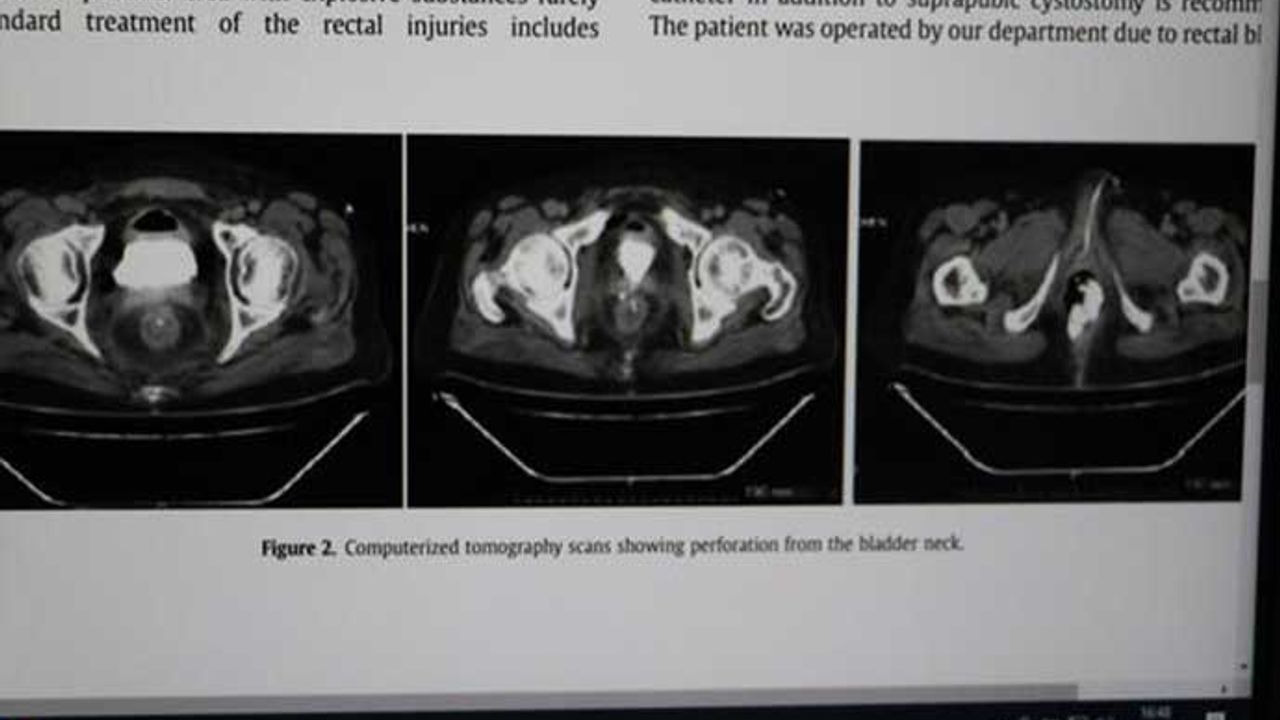

Pamukkale Üniversitesi Hastanesi Üroloji Ana Bilim Dalı Öğretim Üyesi Prof. Dr. Ali Ersin Zümrütbaş, böyle bir olayla tıp tarihinde ilk kez karşılaştıklarını, yaptıkları tedaviyi İngilizce makale olarak önemli bir yabancı dergide yayınlandığını söyledi. Şimdiye kadar atıf gelen en çok yayınlarından biri olduğunu söyleyen Prof. Dr. Zümrütbaş, "2014 yılında 35 yaşında şizofreni hasta getirilmişti. Aynı hasta daha önce de kendi penisini kesmiş ve tedavi edilip, gönderilmiş. Bu sefer de daha önce görmediğimiz şekilde kendisine zarar vermiş, makatına torpil yerleştirmiş, fitilini de ateşleyerek patlatmış. Bu nedenle makatında büyük abdest bölgesi, mesane, prostatı, idrar yolları büyük zarar görmüş. Genel cerrahi bölümüyle birlikte çalışarak zarar gören organları büyük ölçüde onardık. Karnına da büyük abdestini yapabilmesi için torba takılmıştı. Yapılan tedavisinin ardından sağlıklı şekilde taburcu ettik. Böyle bir olayla ilk kez karşılaştığımız için makale olarak yabancı dilde yayınladık. Tıp literatüründe önemli dergi olan 'Urology Case Reports' a yayınlandı. Benim en çok atıf alan yayınlarımdan biri oldu. Vaka ilginç olduğu ve tedavi edilip, taburcu edildiği için tıp literatürüne de girdi" dedi. https://tele1.com.tr/hacamat-yaparken-makatina-cay-bardagi-kacti-397268/